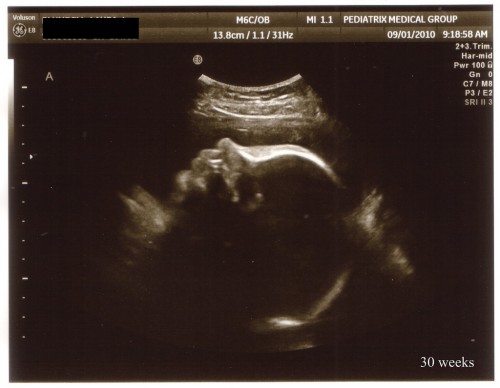

We had our 30 week high risk sonogram to get the boys’ weights and make sure everything is good with them and their growth. They checked my cervix and it was the same as it was when I had it checked last so that’s great news. The boys were a little sleepy this morning so they didn’t really cooperate much and were both hiding their faces. But eventually Baby A (Hayden) turned over and we were able to get a profile shot. He did move a little bit so his nose and forehead are a little elongated.

Baby A profile